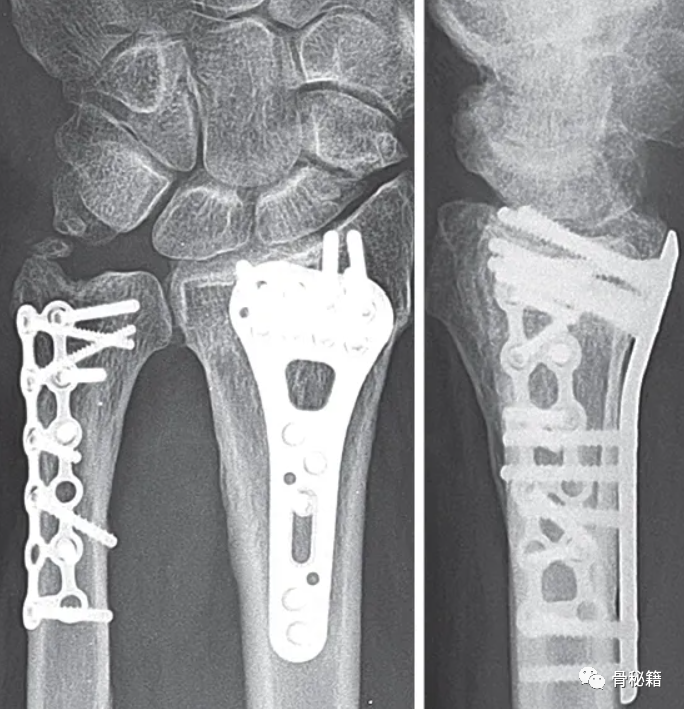

目前最常见的固定方式为:空心螺钉与钢板固定,克氏针等

需要注意的要点:如果桡骨复位不佳,可能导致下尺桡关节匹配问题及相关韧带松弛最终带来相关症状,注意看桡骨尺侧轴线的位置